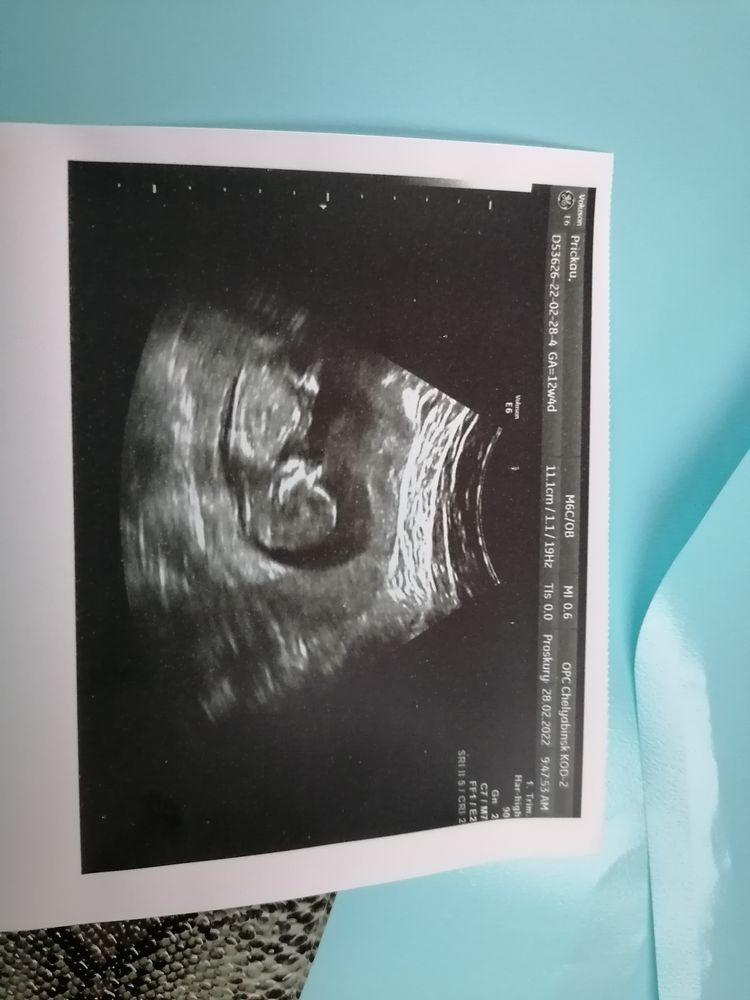

Анна Прицкау

Девочки подскажите пожалуйста,как думаете кто будет, 13 недель, сказали бугорок не видно

28.02.2022